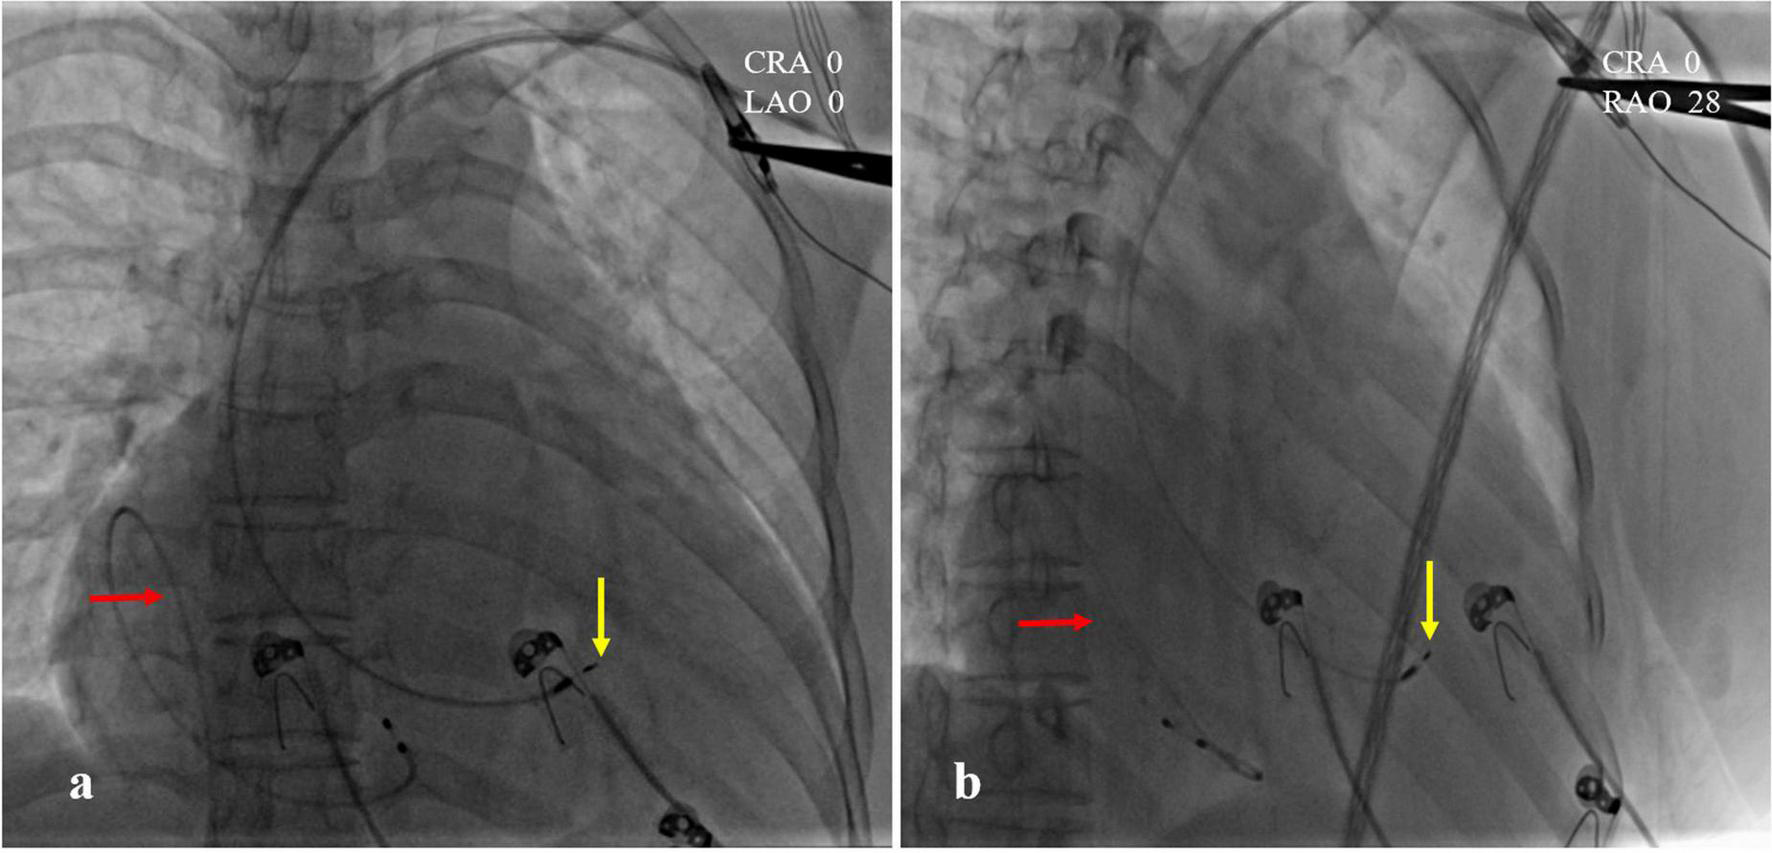

FIGURE 2

Intraoperative X-ray fluoroscopy images. (a) CRA 0, LAO 0; (b) CRA 0, RAO 28. The temporary pacemaker lead was coiled in the right atrial lumen (red arrow). The position of left bundle branch area pacing (LBBaP) was at the distal end of the ventricle, 1.5 cm approximately beyond HIS (yellow arrow).

A 47-year-old female patient was admitted with recurrent syncope for 2 days. Bedside ECG on admission discovered no visible P waves or atrial fibrillatory waves, ventricular escape rhythm with ventricular rate 40–45 bpm, and torsade de pointes. Bedside echocardiography indicated an enlarged heart dominated by the atrium, where the right atrium (RA) size was 8.9 cm × 5.6 cm, the left atrium (LA) size was 7.2 cm × 5.6 cm, the left ventricular end diastolic diameter was 5.1 cm, the left ventricular ejection fraction (LVEF) was 50%, and there was extensive tricuspid regurgitation (Figure 1a). Moreover, only E waves were observed in the early diastolic period, but no A wave was detected in the late diastolic period in the mitral inflow pulse by Doppler recording (Figure 1b). A temporary pacemaker was immediately implanted. However, it was difficult for the temporary pacemaker lead to enter the right ventricle. The patient was instructed to take deep breaths and cough repeatedly. After repeated attempts, the lead was successfully placed into the apex of the right ventricle under the guidance of bedside echocardiography, and the pacing rate was set to 80 bpm. Subcutaneous injection of low molecular weight heparin was administered to prevent blood clots and intravenous infusion of cefazolin sodium was administered to prevent infection. The next day, ECG monitoring indicated ventricular pacing dysfunction, and the lead dislocation of the temporary pacemaker was considered. On the second day, a PPM was implanted. Intraoperative X-ray fluoroscopy showed that the temporary pacemaker lead was dislocated and coiled in the right atrial lumen (Figures 2a,b). Electrophysiology study indicated that no atrial action potential could be recorded in multiple regions of the RA, including right atrial appendage, middle atrial septum, the bottom of the interatrial septum, and low lateral region. Furthermore, there was a lack of atrial capture in several parts of the RA during high output at 5.0 V/0.5 ms, and consequently, atrial activity was considered to be paralyzed electrically (Figure 3a). The decisions to implant a single-chamber PPM and to attempt the LBBaP were made. First, a loach guide wire was delivered to the right ventricular outflow tract, and the His sheath (C315-His, Medtronic, Minneapolis, MN, United States) was delivered to the tricuspid annulus along the guide wire. The unshaped His sheath was difficult to be positioned in place. Through the sheath shaping technology, we put the inner core back into the His sheath, shaped the middle area of the second bend by hand, and adjusted the curvature of the His sheath. Subsequently, the sheath tube was sent to the tricuspid annulus, and an active fixation lead (3830, Medtronic, United States) was sent along the sheath to the right ventricular septum to select an acceptable initial fixation site with an obvious current of injury (Figures 4A,B). A right bundle branch block (RBBB) pattern was clearly observed during ventricular pacing when the lead was screwed into the interventricular septum, which indicated LBBaP (Figures 3b,c), with a stable stimulus to left ventricular activation time (Stim-LVAT) of 68 ms (a sensing of 11.8 mV, a pacing threshold of 0.9 V at a 0.5 ms pulse width and an impedance of 1,002 Ω). After the implantation of the pacemaker (ADSR01, Medtronic, Minneapolis, MN, United States), the temporary pacemaker leads were removed under fluoroscopy. The histology of myocardial biopsy showed hyaline degeneration within the collagen fibers, and the existence of blurred stripes in some myocardial fibers with mucoid degeneration among parallel collagenous fibers (Figure 5). A postoperative ECG showed that ventricular pacing was stable (VVI mode, pacing rate of 60 bpm). Benazepril 5 mg qd was given to improve cardiac remodeling, and apixaban 2.5 mg bid was given to prevent embolism. Ventricular tachycardia did not occur during the postoperative hospitalization. In the postoperative follow-up, the ventricular pacing burden was 96.2%. Pacemaker parameters remained stable with ventricular sensing of 12.5 mV and ventricular pacing threshold of 0.75 V at 0.4 ms. The patient has since remained free of syncope and not experienced cardiac insufficiency.